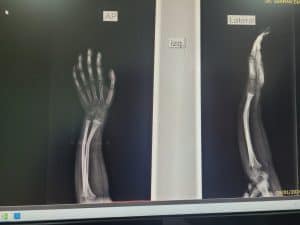

- Fracturas de antebrazo

- Fractura de radio y cubito

Fractura distal de radio

Fractura de radio distal